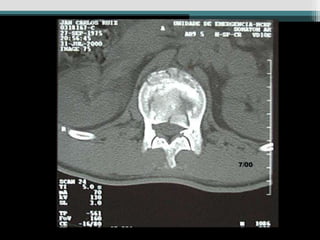

Caso 3 (24 anos, queda Fk e)

Caso 4 (19 anos, auto, Fk e)

Caso 3 (24anos, queda Fk e)

Caso 4 (19anos, auto, Fk e)